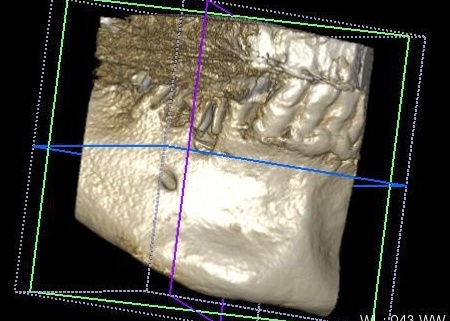

次にCT検査を行い、骨の量や神経の位置を確認したうえでインプラント治療の計画を立てています。

完成した治療計画をもとに、インプラントをあごの骨に埋める手術を実施しました。